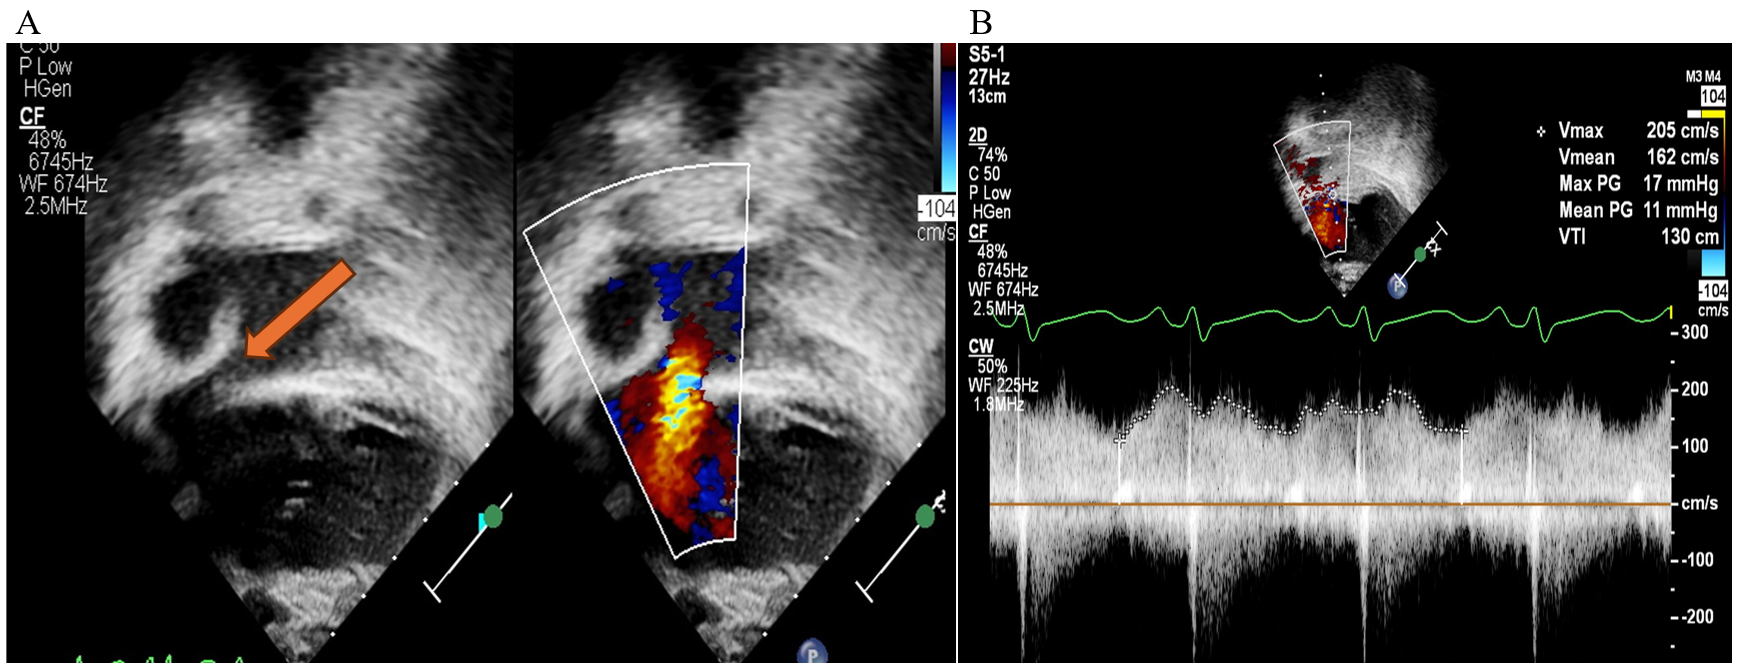

Transthoracic echocardiography (TTE) is essential for evaluating intracardiac anatomy and hemodynamics. In addition, TTE may allow identification of mechanical contributors to PLE, such as a restrictive atrial septum (Figure 4). Significant AVV regurgitation or SV systolic dysfunction may preclude effective surgical TDD, with OHT being the more appropriate strategy.

Figure 4: TTE Images of a Fontan Patient With Early-Onset PLE After a Fontan Procedure

Figure 4

(Panel A) 2D and color flow interrogation of the atrial septum in a 5-year-old Fontan patient (tricuspid atresia with l-TGA) who developed PLE within a few months after an extracardiac Fontan surgery. The orange arrow points to narrowing of the ASD. Color flow Doppler suggests accelerated flow with restriction of the atrial septum. (Panel B) Spectral Doppler across the ASD in the same patient confirms restriction of the atrial septum showing elevated MG 11 mm Hg across the ASD, later confirmed by CC. He subsequently underwent surgical revision of his Fontan pathway.

2D = two-dimensional; ASD = atrial septal defect; CC = cardiac catheterization; l-TGA = levo-transposition of the great arteries; MG = mean gradient; PLE = protein-losing enteropathy; TTE = transthoracic echocardiographic.